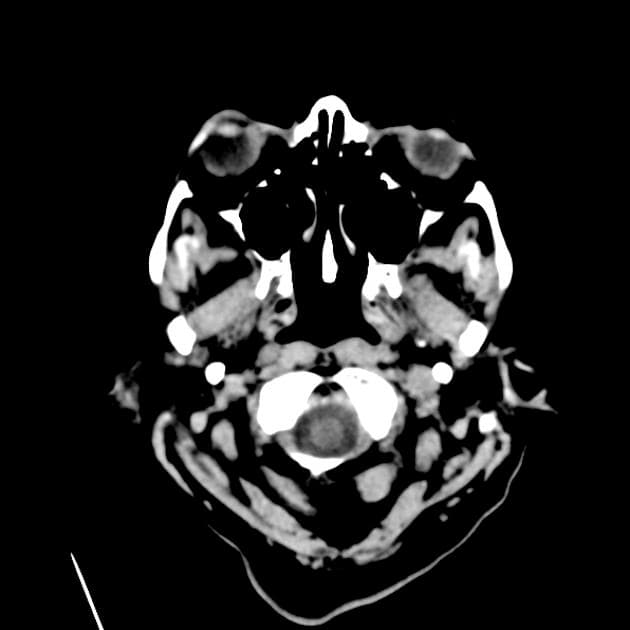

Axial ADC

- Khối bắt thuốc dạng viền (ring-enhancing mass) ở thuỳ trán sau bên trái, kèm theo một lượng nhỏ phù vận mạch (vasogenic edema) xung quanh.

- Có một phần hạn chế khuếch tán (diffusion restriction) ở vùng ngoại vi, nhưng không có ở trung tâm.

Lesion "hoàn hảo" bắt thuốc dạng viền, nhưng không phải là áp xe não (do không có hạn chế khuếch tán ở trung tâm trên hình ảnh khuếch tán – DWI và lượng phù tương đối ít). MAGIC DR là từ viết tắt gợi nhớ hữu ích cho hình ảnh này.